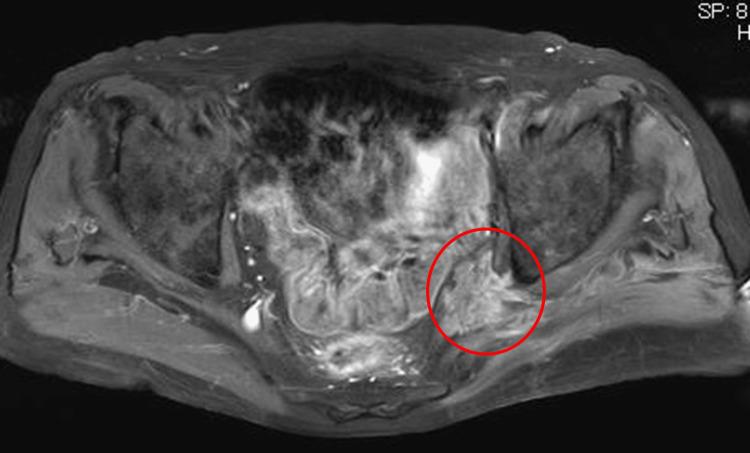

An 81-year-old man with a history of prostate cancer developed sciatica and underwent L4/5 laminectomy followed by L5/S1 transforaminal lumbar interbody fusion. Postoperatively, pain improved temporarily, then deteriorated. Tumor resection was performed after enhanced magnetic resonance imaging showed a mass distal to the left greater sciatic foramen. Histopathological examination showed the perineural spread of prostate cancer to the sciatic nerve. Developments in diagnostic imaging have revealed that prostate cancer can undergo perineural spread. Imaging studies are essential when sciatica is diagnosed in patients with a history of prostate cancer.

一名患有前列腺癌病史的81岁男性出现坐骨神经痛,接受了L4/5椎板切除术,随后进行了L5/S1经椎间孔腰椎椎间融合术。术后,疼痛暂时改善,但随后恶化。增强磁共振成像显示左侧坐骨大孔远端有肿块后,进行了肿瘤切除术。组织病理学检查显示前列腺癌向坐骨神经的神经周围扩散。诊断成像技术的发展表明前列腺癌可发生神经周围扩散。对于有前列腺癌病史且被诊断为坐骨神经痛的患者,影像学检查至关重要。